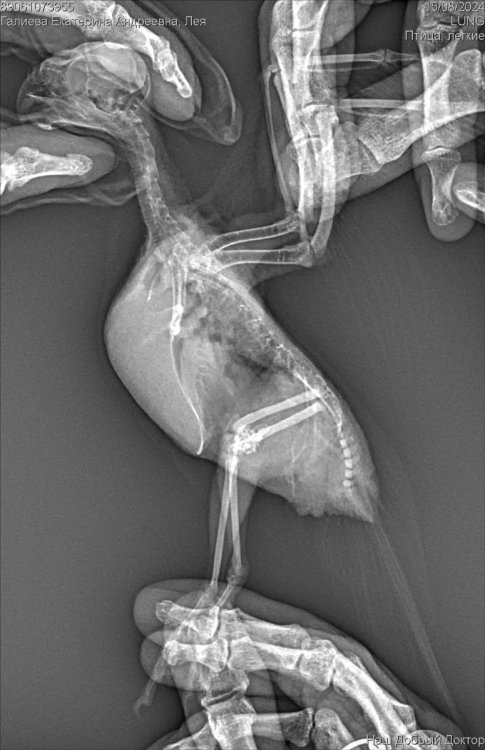

Рекомендован был рентген, по рентгену орнитолог сказала , что к попугая :

Аэросаккулит(воспаление

воздушных мешков), пневмония, нефрит, гепатомегалия, повышенная плотность костей связана с гиперестрогенизмом

Если здесь есть орнитологи, прошу помогите пожалуйста, я была на консультации 3 врачей, я боюсь давать своей птичке Амоксиклав и тербинафин целый месяц. Не много ли это ? Как вы считаете ? И пожалуйста посмотрите рентген умоляю, скажи , что вы видите ? Насколько плохой анализ помета ? И насколько серьезны поставленные диагнозы? И возможно ли это вылечить?  Остальные анализы как придут, я приложу фотографии.

Автор после рождения яйца (а оно 100% не будет единственным,там хороший такой яичник виден)- разумеется и эпителий, и лейкоциты,и эритроциты будут в помете.